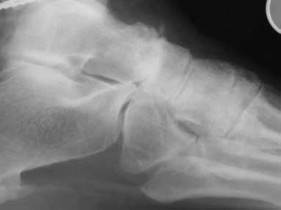

Question 29

A 32-year-old male falls from a ladder and sustains a Hawkins Type III fracture of the talar neck. By definition, a Hawkins Type III injury involves a talar neck fracture accompanied by which of the following patterns of dislocation?

The Hawkins classification describes talar neck fractures: Type I is nondisplaced; Type II involves subtalar subluxation or dislocation; Type III involves dislocation of both the subtalar and tibiotalar (ankle) joints (the talar body extrudes posteromedially); Type IV (added by Canale) involves dislocation of the subtalar, tibiotalar, and talonavicular joints. The risk of avascular necrosis (AVN) increases substantially with each grade, approaching 100% in Type III/IV if not reduced urgently.